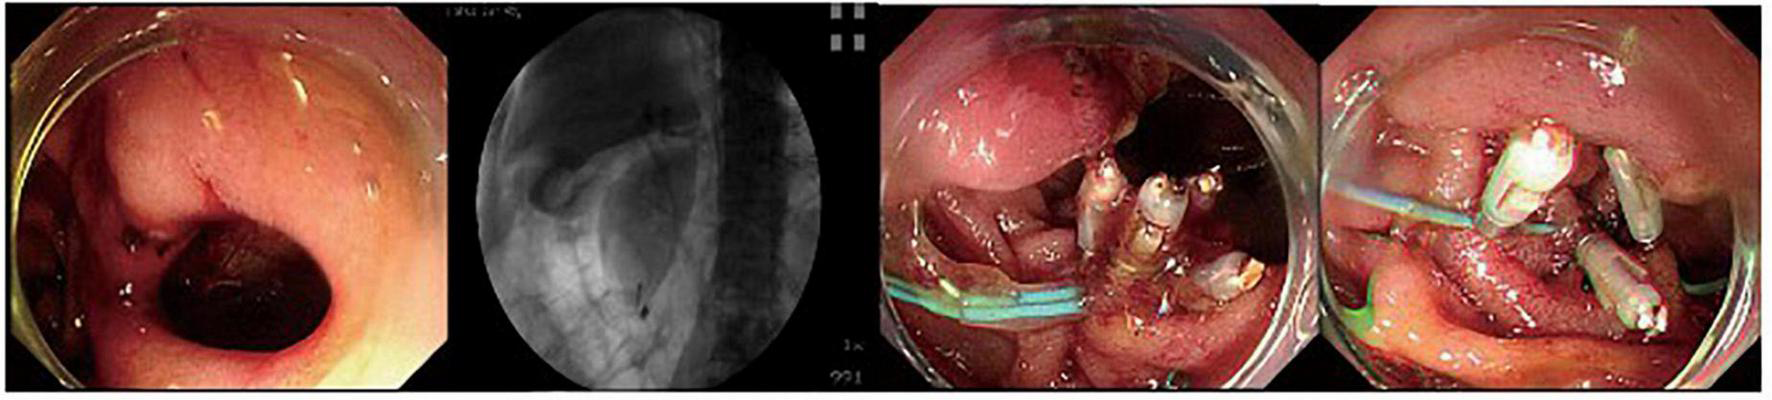

FIGURE 1

A duodenal wall perforation closed by clips and nylon rope under a single cavity forward-viewing endoscope. The perforation had only signs of retroperitoneal perforation.

The fundus perforation, the peri-ampullary diverticulum perforation, and eight duodenal perforations were treated by closing the lesion, performing endoscopic nasobiliary drainage (ENBD) or endoscopic retrograde biliary drainage (ERBD), conducting gastrointestinal decompression, and using proton pump inhibitor (PPI), somatostatin (SS), and broad-spectrum antibiotics for 5–7 days. Each lesion was closed by clips, purse string sutures, or over-the-scope-clip (OTSC) (Figures 1–3). Three afferent limb perforations and three duodenal wall perforations were treated through surgery. The small bile duct perforation on the liver surface, the residual duct of gallbladder perforation, and the 26 peri-ampullary perforations were healed through nasobiliary drainage or biliary stenting drainage, gastrointestinal decompression, and using PPI, SS, and broad-spectrum antibiotics for 5–7 days. Biliary stents are typically 8.5 Fr × 7 cm in size, whereas pancreatic stents are typically 5 Fr × 5 cm in size. If no unusual conditions exist, the stents will be removed after 1 month of satisfactory drainage. Three patients received endoscopic retrograde pancreatic drainage (ERPD) at the same time. The 81-year-old female patient with a duodenal wall perforation, which had been closed with OTSC, died of heart failure and post-ERCP pancreatitis 3 days after the ERCP procedure. The other patients recovered successfully (Figure 4). Management outcomes of the 45 patients were summarized in Table 3. The mortality was 2.2% (1/45).